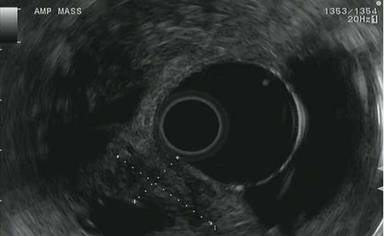

The patient was referred to the University of Colorado to establish tissue diagnosis and for an attempted endoscopic resection given his age and comorbidities. On repeat ERCP, an ampullary mass was identified involving the major papilla (Figure 1). A localized distal biliary stricture was also found which did not have the appearance of intraductal growth of an ampullary mass. Endoscopic ultrasound confirmed the presence of the ampullary mass causing a stricture (mass 2.2 cm in largest diameter; Figure 2). The stricture was in the very downstream common bile duct, felt to be entirely within the intra-duodenal portion, and EUS showed no definite submucosal invasion. Endoscopic biopsies were suspicious for adenocarcinoma, but without definite invasion; it was not felt that brushings would add any useful information at this point. After a lengthy discussion of treatment options, the patient elected for an attempt at endoscopic ampullectomy rather than proceeding directly to surgery. Endoscopic ampullectomy was performed with a polypectomy snare in multiple segments (Figure 3). Histologic analysis demonstrated periampullary/duodenal dysplasia (adenoma) associated with invasive carcinoma limited to the ampulla. Immunohistochemistry demonstrated positive staining for CK20 and CDX2 and negative staining for CK7. Based on the combined findings of duodenal dysplasia and immunoreactivity for CK20 and CDX2, the carcinoma was classified as intestinal-type. Invasive carcinoma was widely present at the cauterized tissue edges. No lymphovascular invasion was identified.

Figure 2. EUS showed a 12x22 mm hypoechoic oval mass in the ampulla, with well-defined endosonographic borders. |